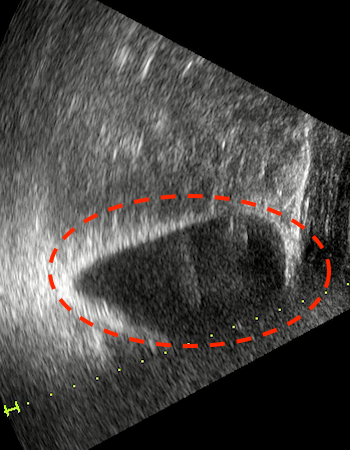

姿勢正しく座っていると、ぼう胱が他の内臓に押さえつけられて数値が増えにくいことがあります。

いまの幾代さんのぼう胱はこんな感じになっているかもしれません。

※正常なぼう胱 ※潰れたぼう胱

なるほど~。こんな時はどうしたらいいですか?

そんな時は「補助計測」を使ってみましょう。

また装着した時と同じ120°の姿勢をとって、補助計測ボタンを押してみて下さい。